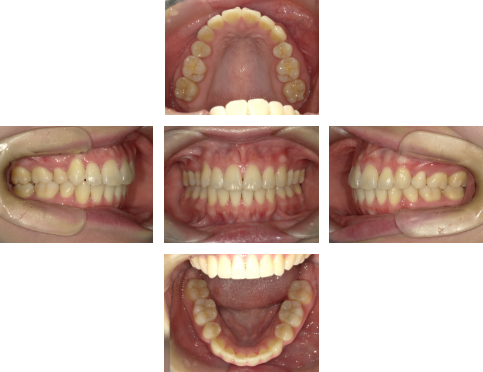

【治療終了時】

前歯の後方移動により、口唇の突出感が改善しました。また、上下の歯が正しい位置で噛み合うようになり、機能面、審美面ともに改善が認められました。

Eラインも整い、口元の印象が変化がお分かりいただけるかと思います。